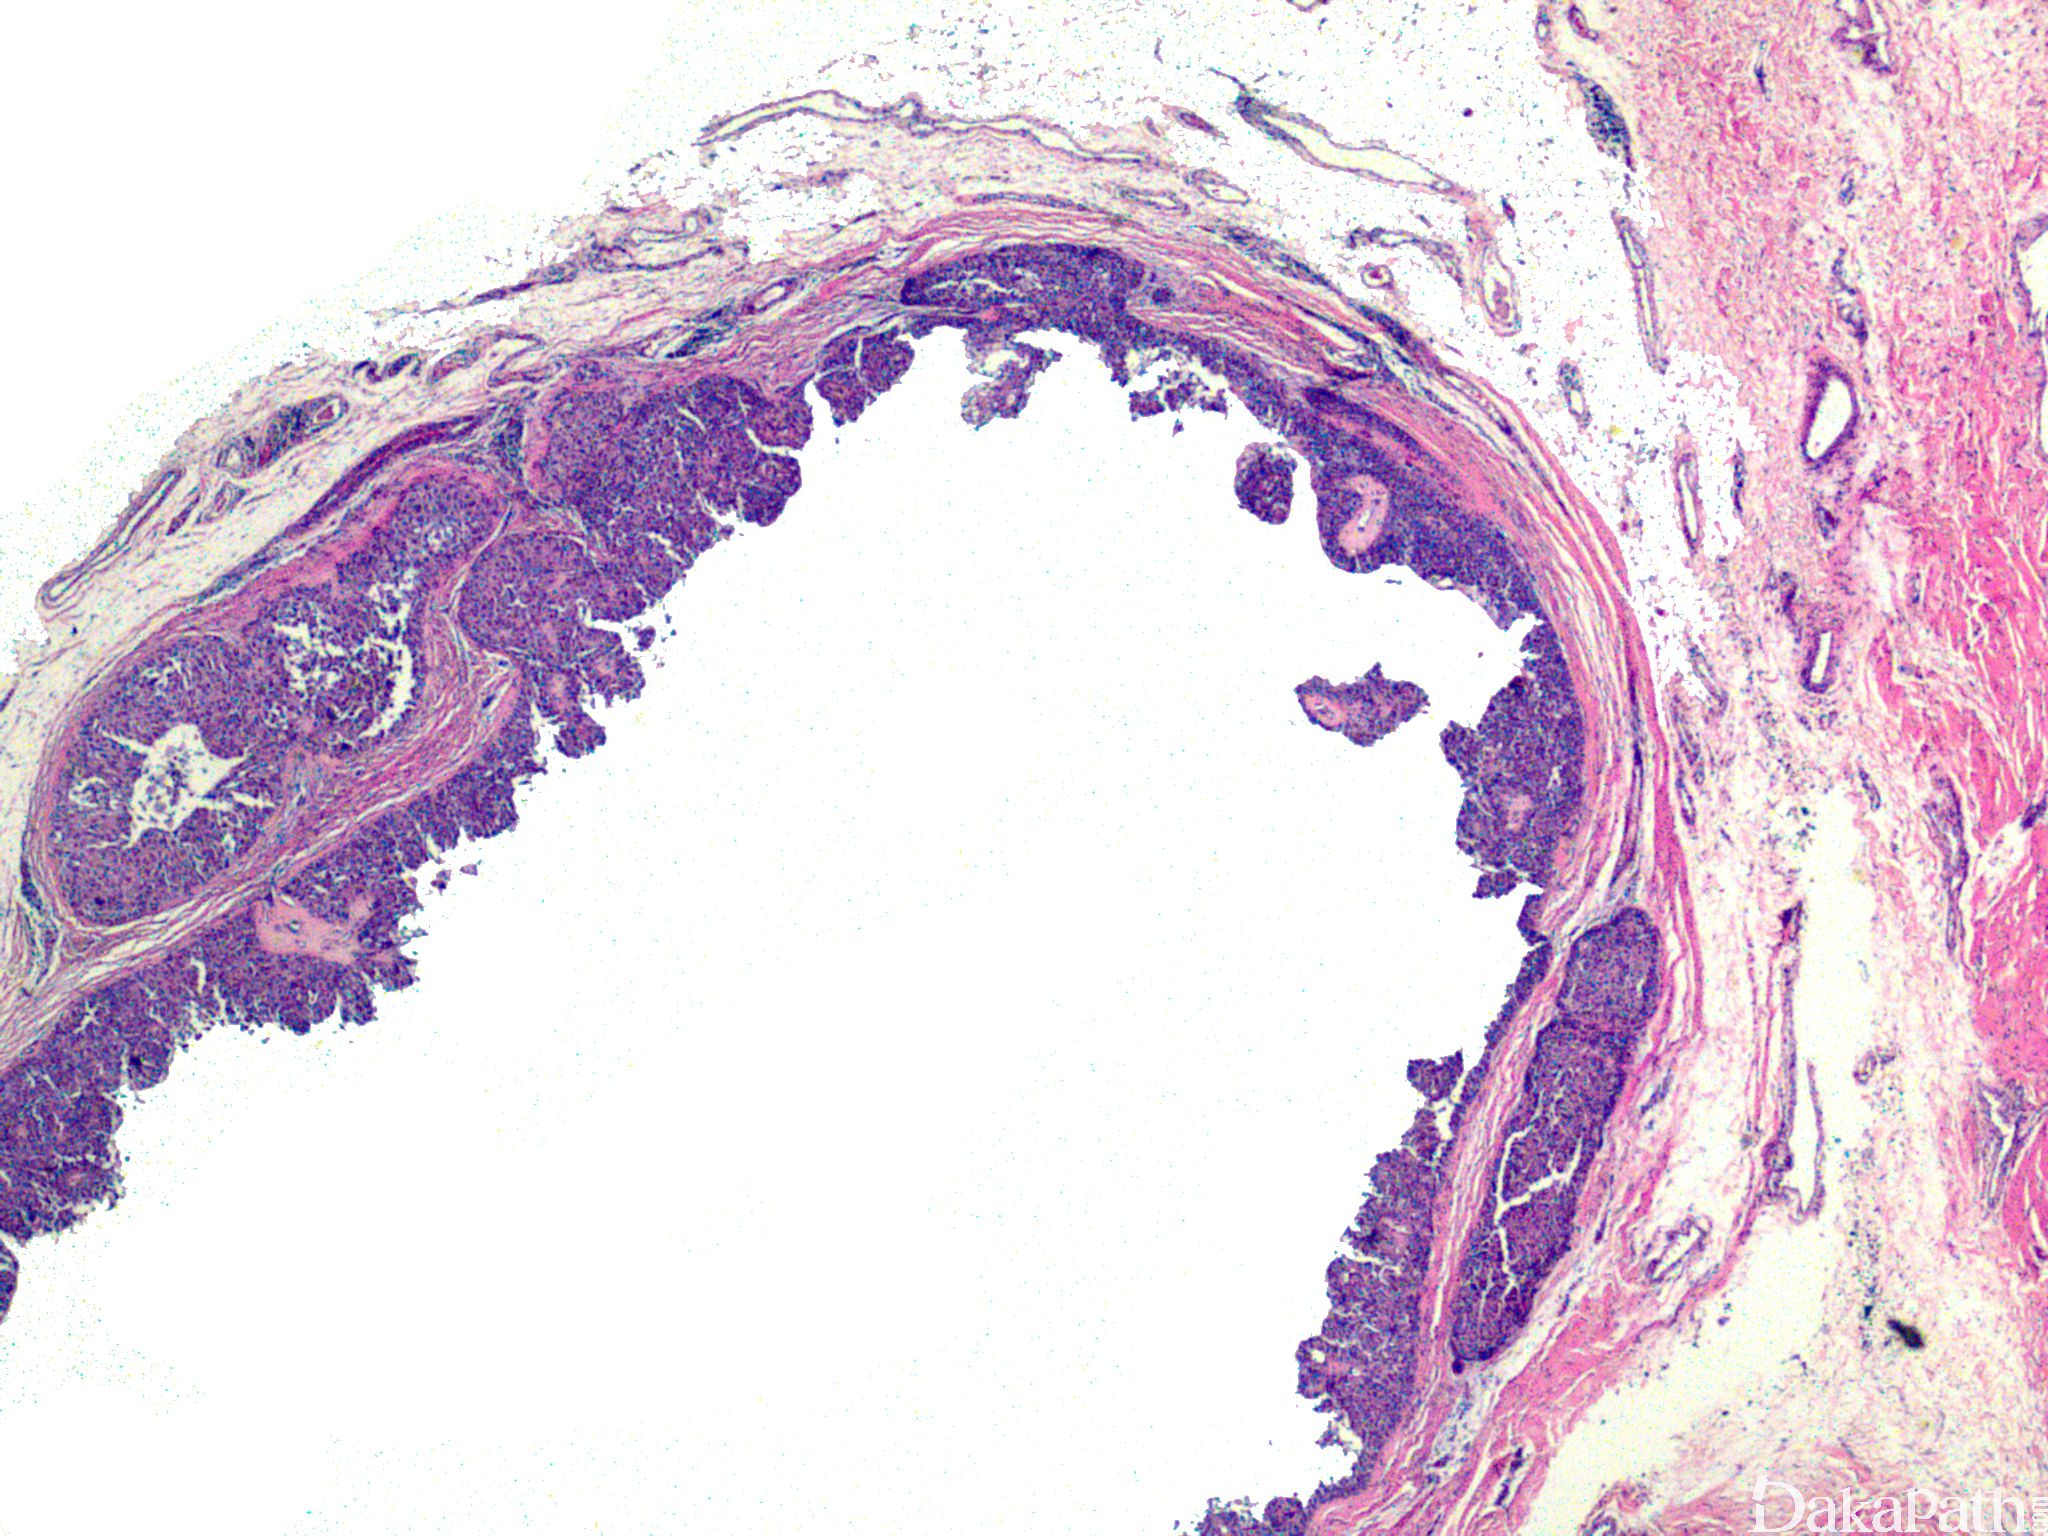

具有典型汗腺瘤形态学特征,呈囊性结节性生长,具透明细胞、鳞样细胞、肌上皮细胞等多种细胞成分;

可见小腺管及上皮细胞内小泡;

具浸润性生长方式;